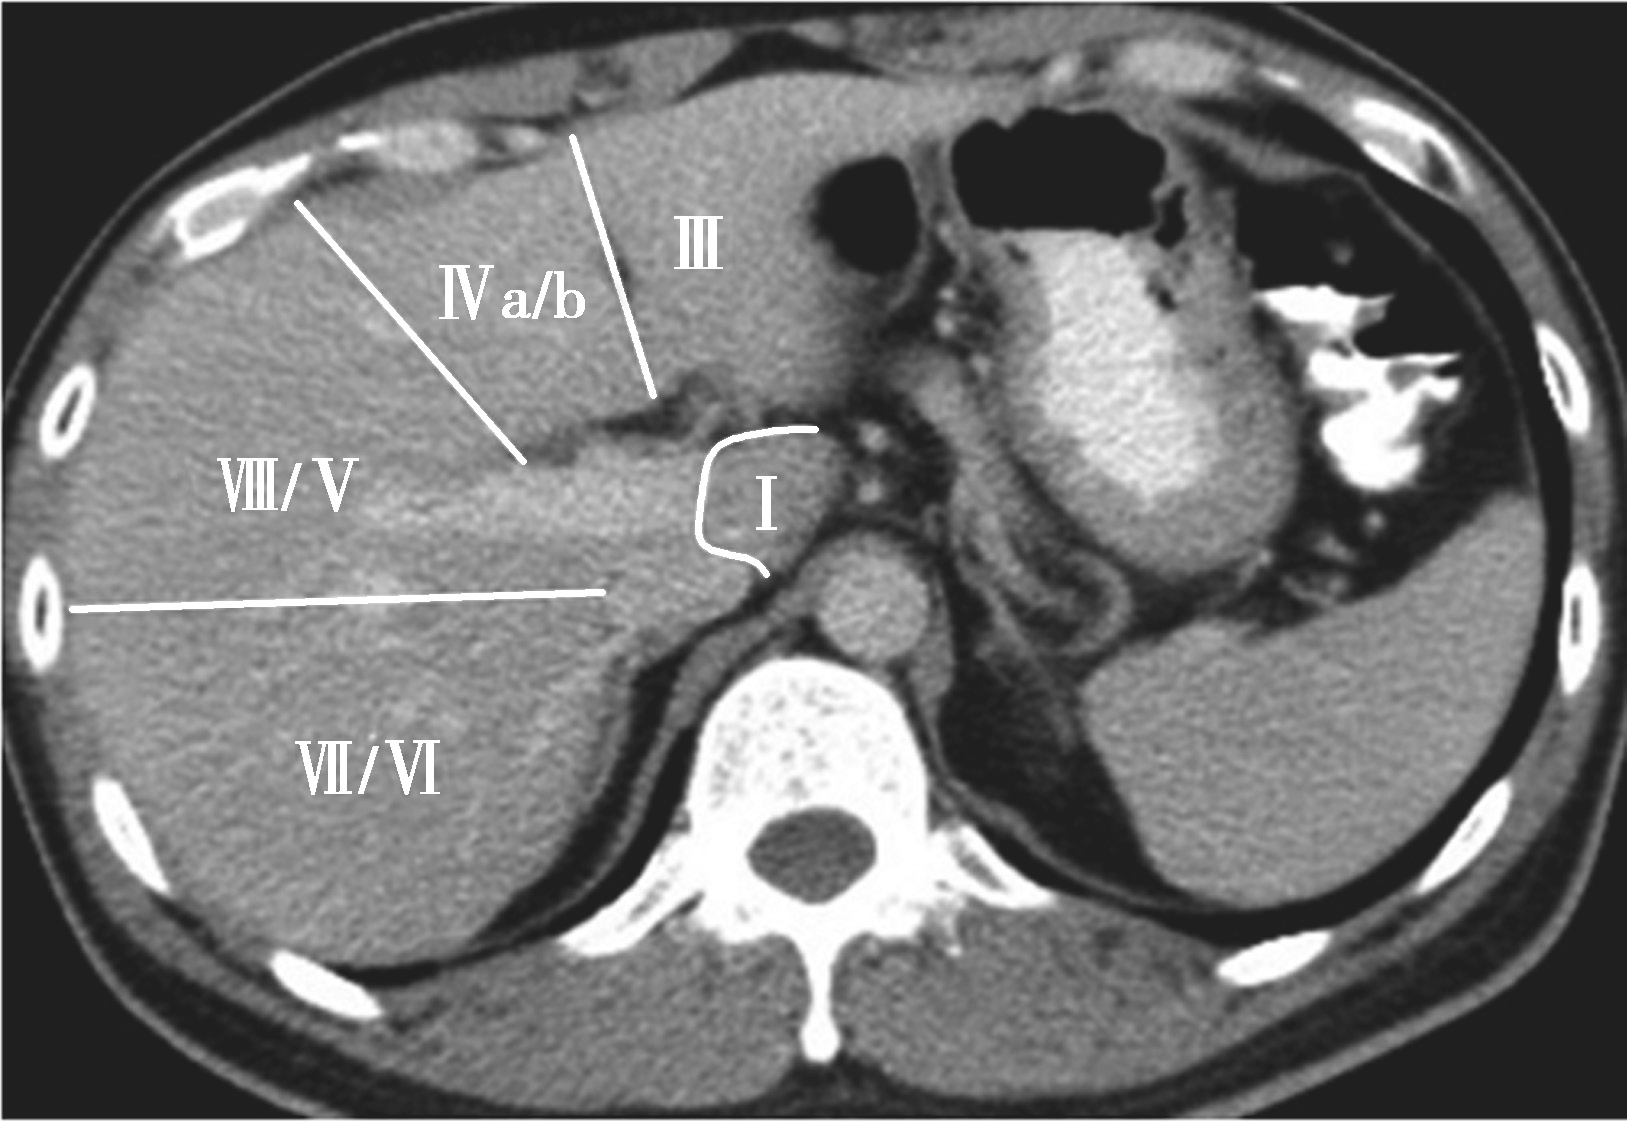

(3)肝8段划分法(图5-21-35):

Couinaud根据门静脉及肝静脉的分布将肝脏分为8段,门静脉分布于肝段内,肝静脉分布于肝段间。8分段法是临床外科和影像最为常用的分段法。以肝中静脉为界分为左、右半肝;以肝左静脉为界将左半肝分为左内(Ⅳ段)和左外叶(Ⅱ段+Ⅲ段);左外叶以门静脉左支为界水平分为上(Ⅱ段)下(Ⅲ段)两段;以肝右静脉为界分右半肝为前叶(Ⅷ段+Ⅴ段)和后叶(Ⅵ段+Ⅶ段);以门静脉右支为界将右肝横向分为上下两段分别为右前上段(Ⅷ段)、右前下段(Ⅴ段),右后下段(Ⅵ)和右后上段(Ⅶ段);肝尾状叶为单独一段(Ⅰ段)。

图5-21-35 肝8段划分法示意图